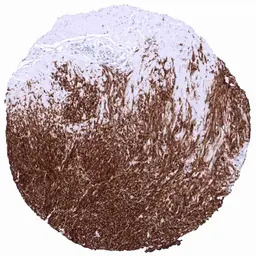

IHC-P analysis of human gastrointestinal stromal tumor tissue section using GTX04369 TMEM16A antibody [MSVA-201M] HistoMAX.

Tumor periphery of a GIST showing intensive TMEM16A staining in all tumor cells.